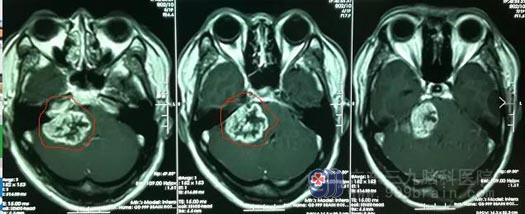

▲林某影像检查

结合检查结果和临床表现,鲁明认为患者颅内占位是听神经鞘瘤的可能性很大。随后,鲁明团队为患者实施了右侧乙状窦后入路桥小脑角区占位性病变切除术。目前林某恢复良好,耳鸣的症状已经消失,右耳听力较术前有明显提高。